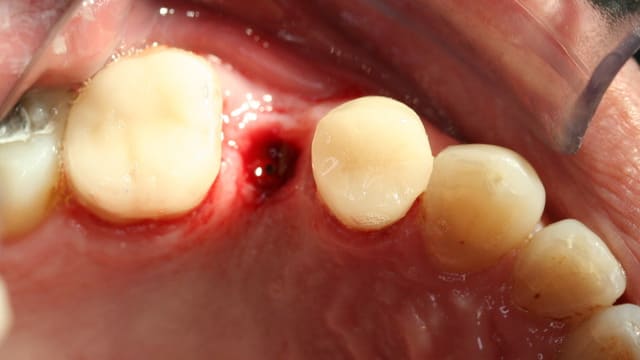

Pour ceux que ca interessent, et parce qu on a m a demandé des cas supplémentaires dans le sujet 23 implants rehabilitation totale, voici un autre cas d implantation immédiate avec la technique minimalement invasive et condensation grace aux forets.

Le patient a reçu un traitement il y a dix ans dans le maxillaire et dans le 4eme quadrant.Comme on peut le voir j´ai du extraire quelques dents au maxillaire: 35 37 et 45.

Le septum de la 37 a été foré avec un foret conique 3 faces.

J ai planté à 60 Ncm sans fracturer le septum.Juste après l opération , les prep caps en zircon ont été cémenté.La restauration définitive 34 jusqu` à 37 été fixé 2 semaines après l implantation avec implantlink (detax). Après un an, le bridge a été retiré facilement pour voir l´état de la gencive et faire une radio de contrôle.On la re ossifiction est satisfaisante et que la gencive "aime" le zircon.

Le bridge a ensuite été recémenté sans correction nécessaire du bridge.